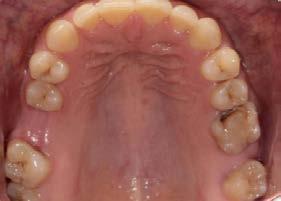

Caso clínico: paciente femenino de 19 años, patrón dolicofacial, perfil convexo, clase II esqueletal debido a una retrusión mandibular, mordida abierta anterior esqueletal, clase II molar, clase canina no establecida por mordida abierta, apiñamiento severo superior e inferior y deglución atípica.

Resultados: obtención de una clase canina I y clase molar II funcional, se corrigieron las sobremordidas horizontal y vertical, y se logró la coincidencia de líneas medias facial y dental. El manejo de la mordida abierta anterior se llevó a cabo por medio de la corrección del hábito de deglución atípica con la ayuda de spikes de resina, elásticos intermaxilares y arcos utility, y se obtuvieron buenos resultados estéticos, dentales y funcionales.